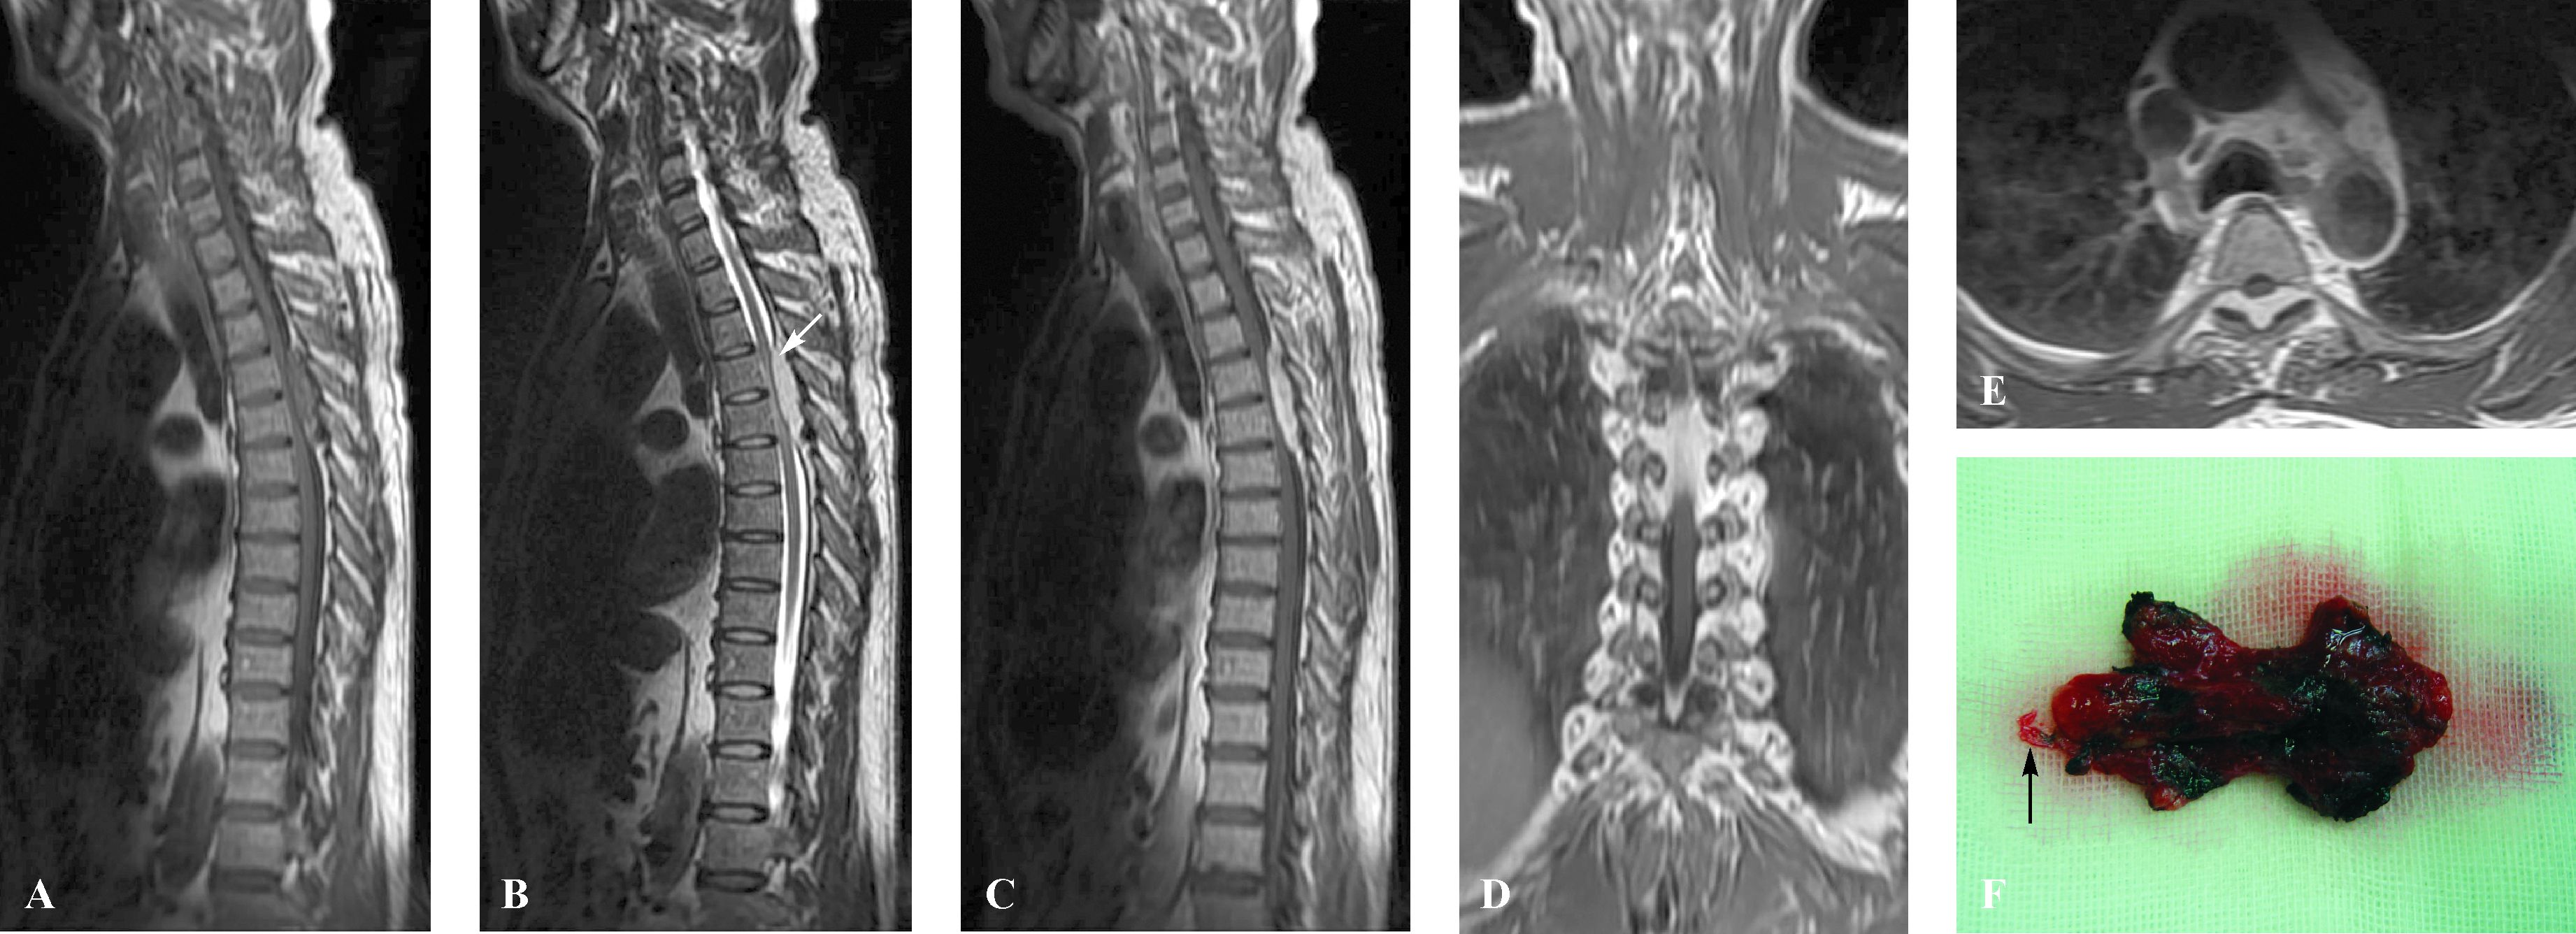

1 病例摘要患者,男性,55岁,因“进行性双下肢酸麻、乏力7月余”于2012年3月5日入院。检查:右侧下肢肌力Ⅳ级,左侧下肢肌力Ⅳ+级,T5水平以下深浅感觉减退,肌张力正常,双侧巴宾斯基征阳性。胸椎MRI显示:T3-6水平椎管内背侧、硬脊膜外呈稍长T1稍长T2信号占位性病变,大小约73mm×11mm,增强后明显强化,伴有“鼠尾征”。在冠状位可见肿块向两侧椎间孔延伸,轴位可见肿块呈“钳状”包绕压迫脊髓(图1A~E)。诊断为T3-6水平椎管内硬脊膜外占位性病变,考虑为脊膜瘤。于全身麻醉下施行椎管内探查、病变切除术。打开椎板后可见紫红色肿瘤组织,有包膜,边界清,表面呈桑椹颗粒样。肿瘤包膜张力高,易出血,质地稍韧。肿瘤完全位于硬膜外腔,向两侧延伸至椎管侧方、向椎间孔生长。肿瘤下极背侧有一条较粗大的引流血管(图1F)。肿瘤与硬脊膜轻度粘连,椎体骨质无受累。显微镜下沿肿瘤边界逐步电凝分离并全切肿瘤。硬脊膜完整,受压明显。组织病理学检查结果:海绵状血管瘤(图2)。患者术后恢复顺利,症状完全消失。随访两年无异常。

| A、B、C显示T3-6水平椎管后部硬脊膜外“长梭状”占位病变,其中A为胸椎矢状位(平扫),稍长T1信号; B为胸椎矢状位(平扫),稍长T2信号,可见肿瘤前方线状低信号的硬脊膜(白箭头所示); C为胸椎矢状位(增强),肿瘤注药后明显均匀强化,伴“鼠尾征”. D:胸椎冠状位(增强),肿块向两侧椎间孔延伸. E:胸椎轴位(增强),肿块呈“钳状”包绕压迫脊髓. F: 肿瘤标本大体观显示全切后的形态,尾部一条引流血管(黑箭头所示). 图1 单纯椎管内硬脊膜外海绵状血管瘤的MRI及大体表现 Fig.1 Pure spinal epidural cavernous hemangioma in a 55-year-old man |